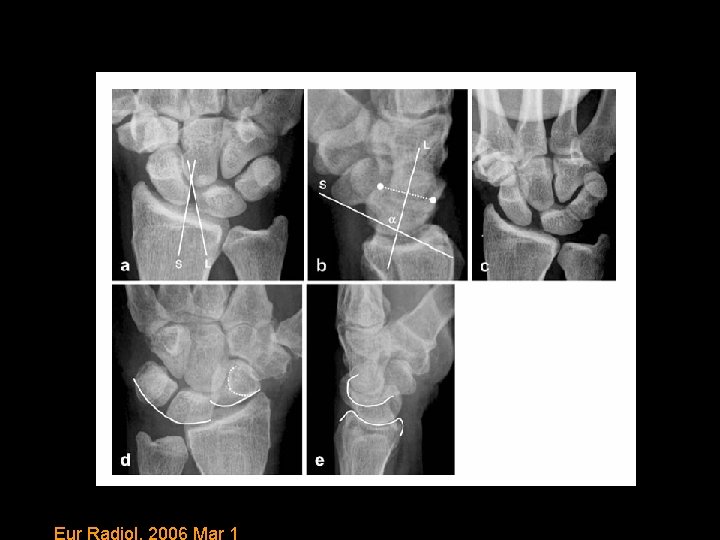

Diagnosis of carpal disorders • Start with plain radiographs to assess alignment. • Articular bones have opposing surfaces 2 mm or less. • Check Gilulas lines. • Three smooth arcs. Disruption in the continuity suggests abnormality at site of broken arc.

Classification of Scapholunate Dissociation Stage I identified with MRI. Stage II diagnosed with stress views with a clenched hand. Stage III and IV demonstrates DISI pattern. Eur Radiol. 2006 Mar 1

Eur Radiol. 2006 Mar 1